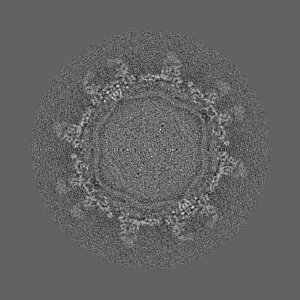

Cryo-EM structure of Dengue virus serotype 2 in complex with antigen-binding fragments of human antibody 2D22

Single-particle6.5 Å

Sample: Dengue virus serotype 2 strain PVP94/07 (a clinical isolate) complexed with Fab fragments of human antibody 2D22.

DENGUE VIRUS. Cryo-EM structure of an antibody that neutralizes dengue virus type 2 by locking E protein dimers.